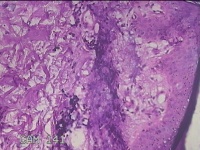

右侧腰臀部包块

性别

女

年龄

44岁

临床诊断

臀部良性肿瘤

一般病史

发现右侧腰臀部包块1个月余。

标本名称

大体所见

灰白粉红色包块0.8x0.3x0.2cm一个,表面光滑。

图2

良性病变。